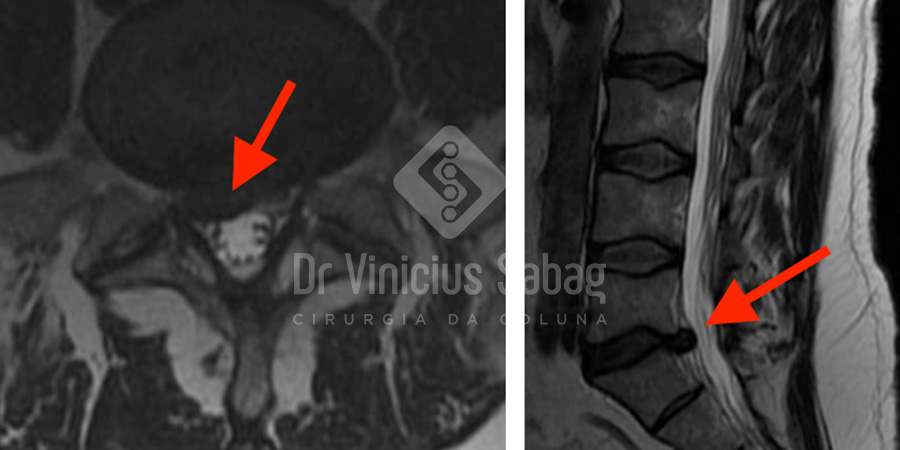

Chegou ao consultório já portando uma ressonância magnética solicitada previamente. O exame demonstrou uma hérnia discal L5-S1 comprimindo a raiz nervosa direita, compatível com o quadro clínico de dor irradiada e dificuldade para permanecer em pé e caminhar.

Ressonância magnética evidenciando hérnia discal L5-S1 à direita com compressão neurológica.